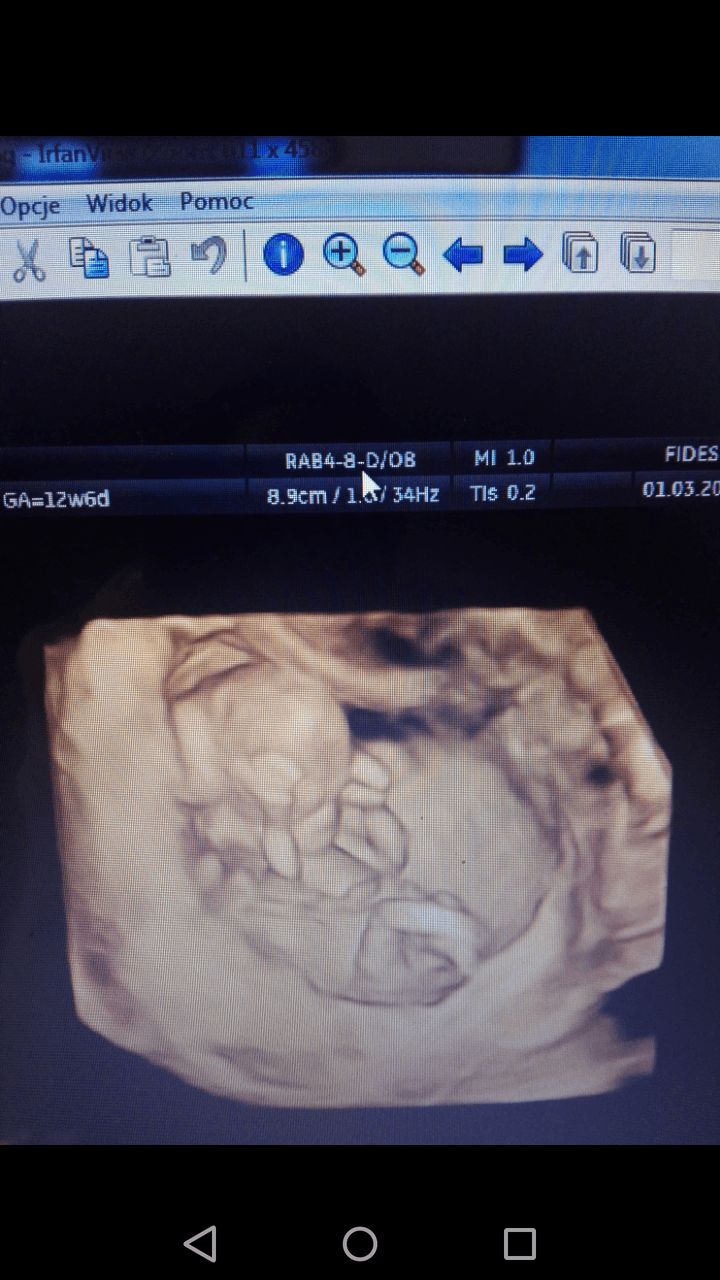

Hej Dziewczyny .Czy moze ktoras z was jest w stanie rozpoznac płec dziecka owego zdjecia usg ? :) za wszystkie odpowiedzi dziekuje

Załączniki

• Screenshot_2019-03-28-12-41-23.png

Screenshot_2019-03-28-12-41-23.png

341,1 KB · Wyświetleń: 1 767